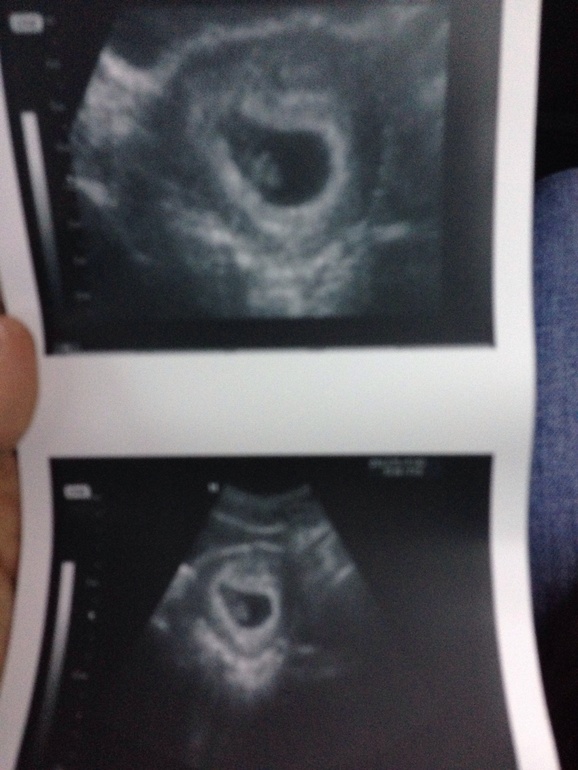

@T.S.Y.B.I.N.A в Благополучная беременность 12 лет Нашей малявочке уже 8 неделек ставят!)) УЗИ, КТГ, доплер Посмотрите еще 20 записей на эту тему Отменить Ответить ☼Таечка☼ 28.01.2014 Ответить Женечка как мило) 27.01.2014 Ответить Елена поздравляю,легкой беременности!!!!! 27.01.2014 Ответить @T.S.Y.B.I.N.A Спасибо!!!))) 27.01.2014 Ответить Сделала скрининг 1 триместра Узи 16-17 недель Чаты Беременных Выберите чат: Январята-2026 Февралята-2026 Мартята-2026 Апрелята-2026 Майчата-2026 Июнята-2026 Июлята-2026 Августята-2026